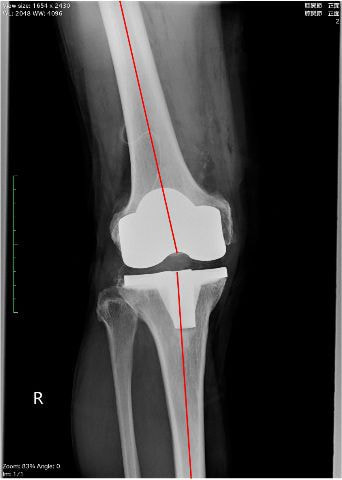

外来通院での運動療法と関節注射を継続して行っていましたが、レントゲンでは膝関節内側の関節軟骨がすり減って、上下の骨が衝突しており、痛みも強いことから手術適応となりました。(左写真)

術後3日目から松葉杖歩行を開始しました。人工膝関節置換術後はO脚が改善し(右写真)、右脚に体重をかけて歩くことも早期に可能になります。術後5日目には、松葉杖を使用せずに両脚で歩くことが可能になりました。入院中は下肢筋力強化練習や歩行練習を反復することにより、日に日に歩行が安定して行えるようになります。